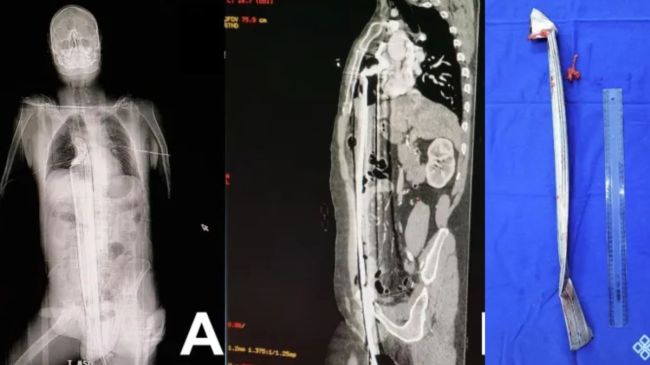

рдпрд╣ рд╢рдЦреНрд╕ рдХрдВрд╕реНрдЯреНрд░рдХреНрд╢рди рд╡рд╛рд▓реА рдЬрдЧрд╣ рдкрд░ 16 рдлреБрдЯ рдКрдВрдЪреЗ рд╕реАрдврд╝реАрдиреБрдорд╛ рд╕реНрдЯреНрд░рдХреНрдЪрд░ рдкрд░ рдХрд╛рдо рдХрд░ рд░рд╣рд╛ рдерд╛ред рдЕрдЪрд╛рдирдХ рдЗрд╕рдХрд╛ рдкреИрд░ рдлрд┐рд╕рд▓ рдЧрдпрд╛ рдФрд░ рдпрд╣ рдиреАрдЪреЗ рдЧрд┐рд░ рдЧрдпрд╛ред рдиреАрдЪреЗ рдХрд░реАрдм 3 рдлреБрдЯ рд▓рдВрдмрд╛ рд░реЙрдб рдХрд╛ рдЯреБрдХрдбрд╝рд╛ рд░рдЦрд╛ рдерд╛ред рдпрд╣ рдЯреБрдХрдбрд╝рд╛ рдЗрд╕ рд╢рдЦреНрд╕ рдХреЗ рдкреНрд░рд╛рдЗрд╡реЗрдЯ рдкрд╛рд░реНрдЯ рдХреЗ рдкрд╛рд╕ рд╕реЗ рд╣реЛрддрд╛ рд╣реБрдЖ рд╢рд░реАрд░ рдореЗрдВ рдШреБрд╕ рдЧрдпрд╛ред рдЗрд╕ рджреМрд░рд╛рди рдпрд╣ рдкреЗрдЯ рдФрд░ рд╕реАрдиреЗ рдХреЛ рдЪреАрд░рддреЗ рд╣реБрдП рджрд┐рд▓ рдХреЗ рдкрд╛рд╕ рдкрд╣реБрдВрдЪ рдЧрдпрд╛ред

рд╢рд░реАрд░ рдореЗрдВ рдШреБрд╕ рдЧрдИ рдереА рд░реЙрдб : рдлреЛрдЯреЛ рдХреНрд░реЗрдбрд┐рдЯ- sciencedirect

рдЗрд╕ рд╢рдЦреНрд╕ рдХреЛ рддреБрд░рдВрдд рд╣реА рд╣реЙрд╕реНрдкрд┐рдЯрд▓ рд▓реЗ рдЬрд╛рдпрд╛ рдЧрдпрд╛ рдЬрд╣рд╛рдВ рдЗрд╕рдХреА рд╕рд░реНрдЬрд░реА рдХреА рдЧрдИред рдпрд╣ рд╕рд░реНрдЬрд░реА рдХрд╛рдлреА рдореБрд╢реНрдХрд┐рд▓ рднрд░реА рдереАред рд╣рд╛рд▓рд╛рдВрдХрд┐ рдбреЙрдХреНрдЯрд░ рдЗрд╕рдореЗрдВ рдХрд╛рдордпрд╛рдм рд░рд╣реЗ рдФрд░ рдЗрд╕ рд░реЙрдб рдХреЛ рдирд┐рдХрд╛рд▓ рджрд┐рдпрд╛ред рдбреЙрдХреНрдЯрд░ рдиреЗ рдЗрд╕ рдХреЗрд╕ рдХреЛ рдХрд┐рд╕реА рдЪрдорддреНрдХрд╛рд░ рд╕реЗ рдХрдо рдирд╣реАрдВ рдмрддрд╛рдпрд╛ред рдЙрдиреНрд╣реЛрдВрдиреЗ рдХрд╣рд╛ рдХрд┐ рдРрд╕реЗ рдХреЗрд╕ рдореЗрдВ рдХрд┐рд╕реА рд╢рдЦреНрд╕ рдХреЗ рдмрдЪрдиреЗ рдХреЗ рдЪрд╛рдВрд╕ рдХрд╛рдлреА рдХрдо рд╣реЛрддреЗ рд╣реИрдВред рд▓реЗрдХрд┐рди рдЗрд╕ рдХреЗрд╕ рдореЗрдВ рд╕рд░реНрдЬрд░реА рдХреЗ рджреМрд░рд╛рди рди рдХреЗрд╡рд▓ рд╢рдЦреНрд╕ рдмрдЪ рдЧрдпрд╛ рдмрд▓реНрдХрд┐ рдЗрд╕реЗ 3 рджрд┐рди рдмрд╛рдж рдЬрдирд░рд▓ рд╡рд╛рд░реНрдб рдореЗрдВ рд╢рд┐рдлреНрдЯ рднреА рдХрд░ рджрд┐рдпрд╛ рдЧрдпрд╛ред рд╕рд░реНрдЬрд░реА рдХреЗ рджреЛ рджрд┐рди рдмрд╛рдж рд╣реА рд╡рд╣ рди рдЪрд▓рдиреЗ рд▓рдЧрд╛ рдФрд░ рдХреБрдЫ рдЪреАрдЬреЗрдВ рдЦрд╛рдиреЗ рднреА рд▓рдЧрд╛ред рдЗрд╕ рдХреЗрд╕ рдХреА рд╕реНрдЯрдбреА рдЗрдВрдЯрд░рдиреЗрд╢рдирд▓ рдЬрд░реНрдирд▓ рдСрдл рд╕рд░реНрдЬрд░реА рдХреЗрд╕ рд░рд┐рдкрд╛реЗрд░реНрдЯ рдореЗрдВ рдкреНрд░рдХрд╛рд╢рд┐рдд рдХреА рдЧрдИ рд╣реИред

рдЬрдм рдЗрд╕ рд╢рдЦреНрд╕ рдХреЛ рд╣реЙрд╕реНрдкрд┐рдЯрд▓ рд▓рд╛рдпрд╛ рдЧрдпрд╛ рддреЛ рдЗрд╕рдХреА рдХрдВрдбреАрд╢рди рдХрд╛рдлреА рдмреБрд░реА рдереАред рдбреЙрдХреНрдЯрд░реЛрдВ рдХреЛ рддреБрд░рдВрдд рд╣реА рд╕рд░реНрдЬрд░реА рдХрд░рдиреА рдкрдбрд╝реАред рдбреЙрдХреНрдЯрд░реЛрдВ рдХреЗ рдореБрддрд╛рдмрд┐рдХ рд╢рд░реАрд░ рдХреЗ рдЕрдВрджрд░ рд╕реЗ рд░реЙрдб рдирд┐рдХрд╛рд▓рдирд╛ рдХрд╛рдлреА рдореБрд╢реНрдХрд┐рд▓ рдХрд╛рдо рдерд╛ рдХреНрдпреЛрдВрдХрд┐ рдЗрд╕ рджреМрд░рд╛рди рдЙрд╕ рд╢рдЦреНрд╕ рдХреЗ рд╢рд░реАрд░ рдХреЗ рдЕрдВрдЧреЛрдВ рдХреЛ рдФрд░ рдЪреЛрдЯ рдкрд╣реБрдВрдЪ рд╕рдХрддреА рдереА рдЬрд┐рд╕рд╕реЗ рдЙрд╕рдХреА рдореМрдд рднреА рд╣реЛ рд╕рдХрддреА рдереАред рдпрд╣ рд░реЙрдб рдЙрд╕ рд╢рдЦреНрд╕ рдХреЗ рд▓реАрд╡рд░ рдФрд░ рдкрд╕рд▓рд┐рдпреЛрдВ рдХреЛ рднреА рдкрд╛рд░ рдХрд░ рдЧрдИ рдереАред рд╣рд╛рд▓рд╛рдВрдХрд┐ рд╢реБрдХреНрд░ рд░рд╣рд╛ рдХрд┐ рдЗрд╕рдиреЗ рджрд┐рд▓ рдХреЛ рдХреЛрдИ рдиреБрдХрд╕рд╛рди рдирд╣реАрдВ рдкрд╣реБрдВрдЪрд╛рдпрд╛ред рд╕рд░реНрдЬрд░реА рдХреЗ рджреМрд░рд╛рди рдорд░реАрдЬ рдХреА рдЧрд░реНрджрди рд╕реЗ рд▓реЗрдХрд░ рдкреЗрдЯ рддрдХ рдХрдЯ рд▓рдЧрд╛рдирд╛ рдкрдбрд╝рд╛ред